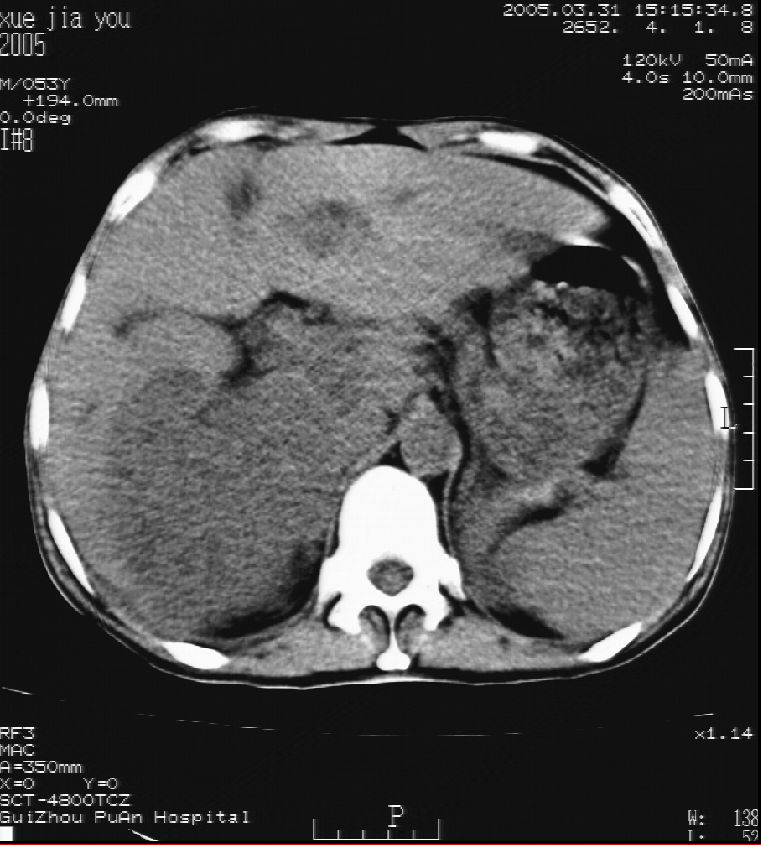

男 55岁  反复上腹痛1年,伴恶心呕吐。2005年做第一次检查后,到外院做b超检查提示肝囊肿,未做任何手术。2006年做过胆总管结石术。骨窗未见异常

这个病灶很有意思,怎么可能没有了呢?我考虑当时很可能是肝脏脓肿(b超示囊肿是有可能误诊的,因为影像表现都是低回声吗?),现在脓肿吸收了,肝脏萎缩,肝裂增宽了.别的肝叶代偿增大,不过现在左内叶的确有个占位,肝内多发结石,脾脏比以前大,不排除有肝硬化可能.建议增强扫描给于定性!!!!

考虑肝内胆管多发结石引起的肝内局部炎症,这样可以解释2005年肝右叶病灶的吸收和左叶新病灶.